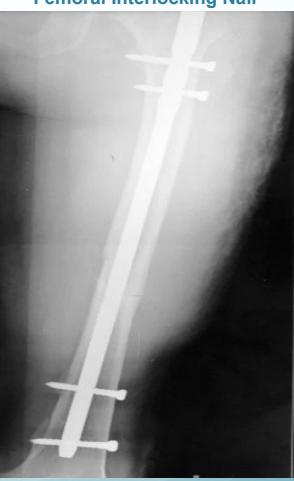

| Inter-locking Nail | Indications: Fractures of long bones. Advantages: Minimally invasive, preserves fracture hematoma, allows early weight-bearing on lower limb. | , , , ![]() |